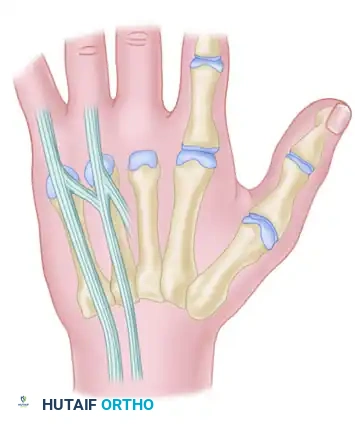

In a landmark cadaver study, the anatomical patterns of the extensors to the fingers were further defined. The most common patterns observed include:

* A single extensor indicis proprius (EIP) inserting to the ulnar side of the index extensor digitorum communis (EDC).

* A single EDC to the index finger.

* A single EDC to the long finger.

* A double EDC to the ring finger.

* An absent EDC to the small finger.

* A double extensor digiti quinti (EDQ) with a double insertion.

FIGURE 66-62: Most common pattern of extensor tendons on the dorsum of the hand, illustrating the single EIP, single EDC to index and long fingers, double EDC to the ring finger, absent EDC to the small finger, and double EDQ.

Extensor indicis proprius (EIP) anatomy, demonstrating its classic ulnar relationship to the EDC of the index finger.